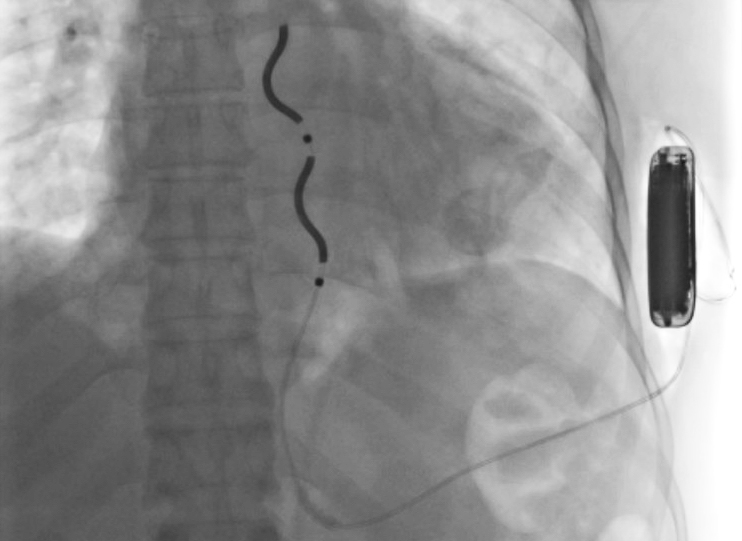

W miejskim szpitalu im. J. Strusia po raz pierwszy wszczepiono pacjentowi defibrylator, który w całości znajduje się poza sercem. To wyjątkowe urządzenie ratuje życie osób z groźnymi arytmiami.

Chodzi o zewnątrznaczyniowy automatyczny kardiowerter-defibrylator EV-ICD. To niewielkie urządzenie, które składa się z dwóch części: elektrody oraz połączonego z nią generatora impulsów. Jego zadanie jest proste: wykryć arytmię - czyli nieregularne bicie serca, które może być groźne dla pacjentów - i za pomocą odpowiedniego impulsu elektrycznego przerwać ją, zanim dojdzie do nieodwracalnych zmian.

W klasycznym kardiowerterze-defibrylatorze elektroda wprowadzana jest przez żyłę bezpośrednio do serca, a pozostała część wszczepiana jest pod skórę. W zewnątrznaczyniowym urządzeniu jest inaczej - całość znajduje się poza mięśniem sercowym.

- W przypadku konwencjonalnego urządzenia ICD elektrodę umieszcza się wewnątrz komory serca za pośrednictwem układu żylnego. Natomiast w przypadku urządzenia EV-ICD elektroda znajduje się pod mostkiem, poza sercem, a EV-ICD umieszcza się pod skórą w okolicy lewej pachy - wyjaśnia dr n. med. Andrzej Bolewski, starszy asystent Oddziału Kardiologii szpitala im. J. Strusia. - Dostęp chirurgiczny niewykorzystujący naczyń i lokalizacji wewnątrzsercowej stanowi najważniejszą podstawową zaletę układu EV-ICD i całkowicie eliminuje wystąpienie powszechnie znanych i niekiedy poważnych powikłań typowych dla układów wewnątrzsercowych (ICD), takich jak niedrożność i niewydolność układu żylnego, uszkodzenie zastawki trójdzielnej czy infekcyjne zapalenie wsierdzia.